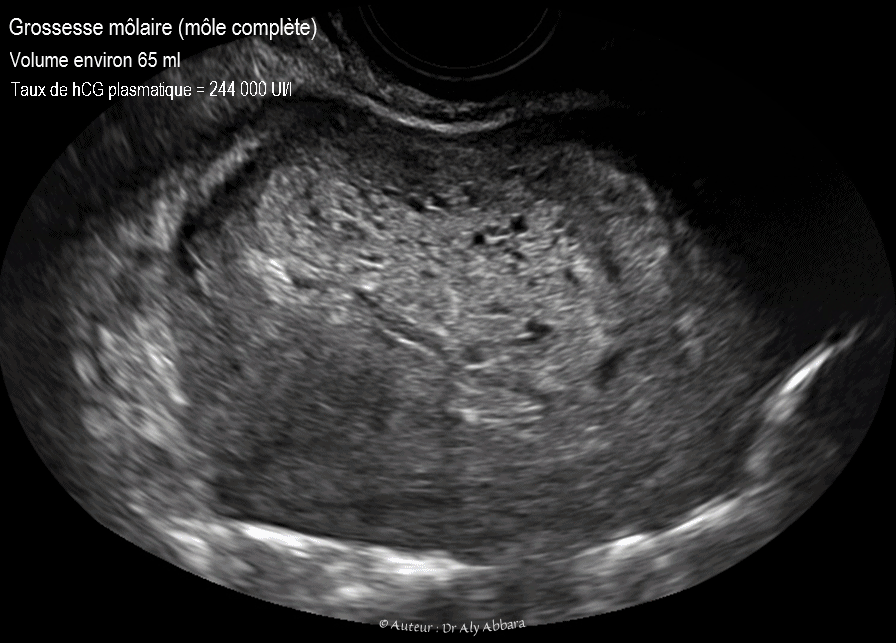

Grossesse môlaire (môle complète) Aspect échographique الحمل العداري أو الرحى العدارية